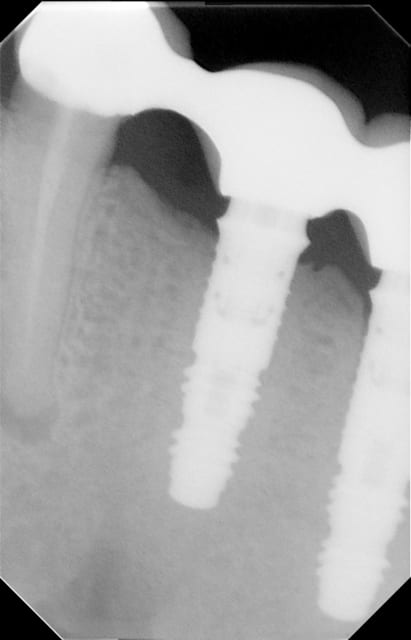

pouvez vous , Oh Grands Maitres en Implanto(to)logie, m'éclairer de vos connaissances :

il me faut refaire un bridge sur ces 3 implants mais ne connait pas ce model .

un indice :la pose date de 1996....

forme caractéristique du frialit 2...

... et la reprise d'endo de la 34....

J'ai cru que c'était un implant champion, induit en erreur par la nature de la suprastructure.